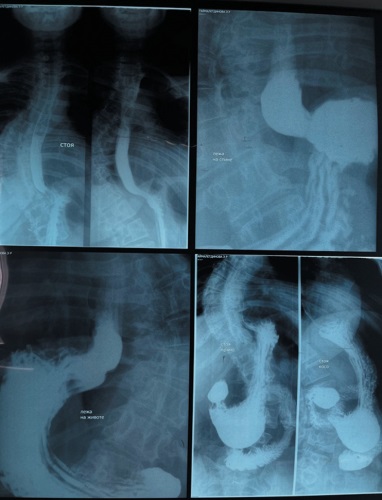

Введение. Грыжа пищеводного отверстия диафрагмы (ГПОД) — это заболевание, при котором происходит ослабление связочного аппарата диафрагмы, в следствие чего происходит растяжение и увеличение пищеводного отверстия диафрагмы, что приводит к выходу органов брюшной полости в плевральную полость. Распространенным методом хирургического лечения ГПОД является лапароскопическая фундопликация по Ниссену с дальнейшем выполнением до или после передней или задней крурорафией. Альтернативным методом является применение робот-ассистированной хирургии. Материалы и методы. С апреля 2022 года по январь 2024 года в торакальном хирургическом отделении Клиники БГМУ выполнено 113 робот-ассистированных лапароскопических фундопликаций. Пациенты были разделены на две группы: Исследовательская группа (n=65): выполнена робот-ассистированная лапароскопическая фундопликация по Ниссену с модифицированной крурорафией и фиксацией манжеты Z-образными швами по патенту № 2813330C1. Контрольная группа (n=48): выполнена стандартная лапароскопическая фундопликация по Ниссену с передней крурорафией узловыми швами. Все оперативные вмешательства выполнены на роботической системы Da Vinci Si. Результаты и обсуждение. Применение патента № 2813330C1 при робот-ассистированных вмешательствах при ГПОД 3 степени предотвращает миграцию манжеты, в том числе и в плевральную полость, соскальзывание и возникновение симптома «телескопа». Позволяет предотвратить деформацию, достичь симметричности и предотвратить соскальзывание манжеты, а также обеспечивает раннюю активацию пациентов и начало энтерального питания за счет использования лапароскопической техники и Z-образного шва нерассасывающимся шовным материалом. Заключение. Проведенные нами оперативные вмешательства при ГПОД 3 степени с применением патента № 2813330C1 и положительные результаты позволяют рассчитывать на то, что предлагаемый нами способ найдет широкое применение в видеоэндоскопической хирургии.